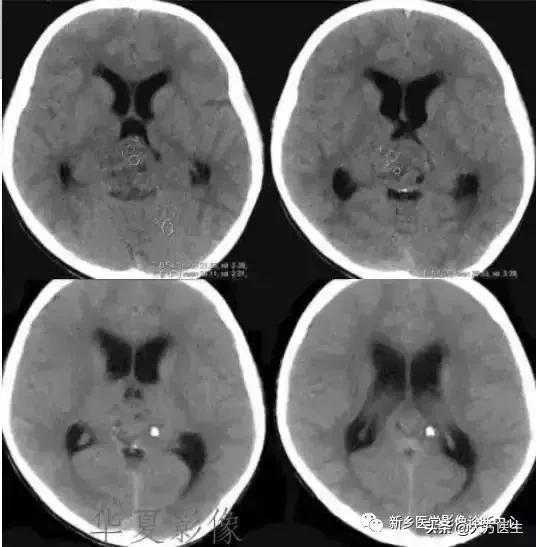

3、颅咽管瘤

多见于20岁以下,常有内分泌代谢障碍及视觉障碍,部分可有颅高压表现。

X:可见鞍区钙化,蝶鞍异常扩大及颅高压征象。CT:见囊实性肿块,囊壁斑块、蛋壳样钙化。MR:T1高等低混杂信号,T2为高信号。

4、生殖细胞瘤

好发于10-20岁女性,松果体区及鞍上区多见。常有头痛、呕吐、视力减退等症状。

CT:颅内压增高症状及松果体区钙化。MR:常为脑三脑室后部长T1长T2信号,水肿不明显。增强明显强化。